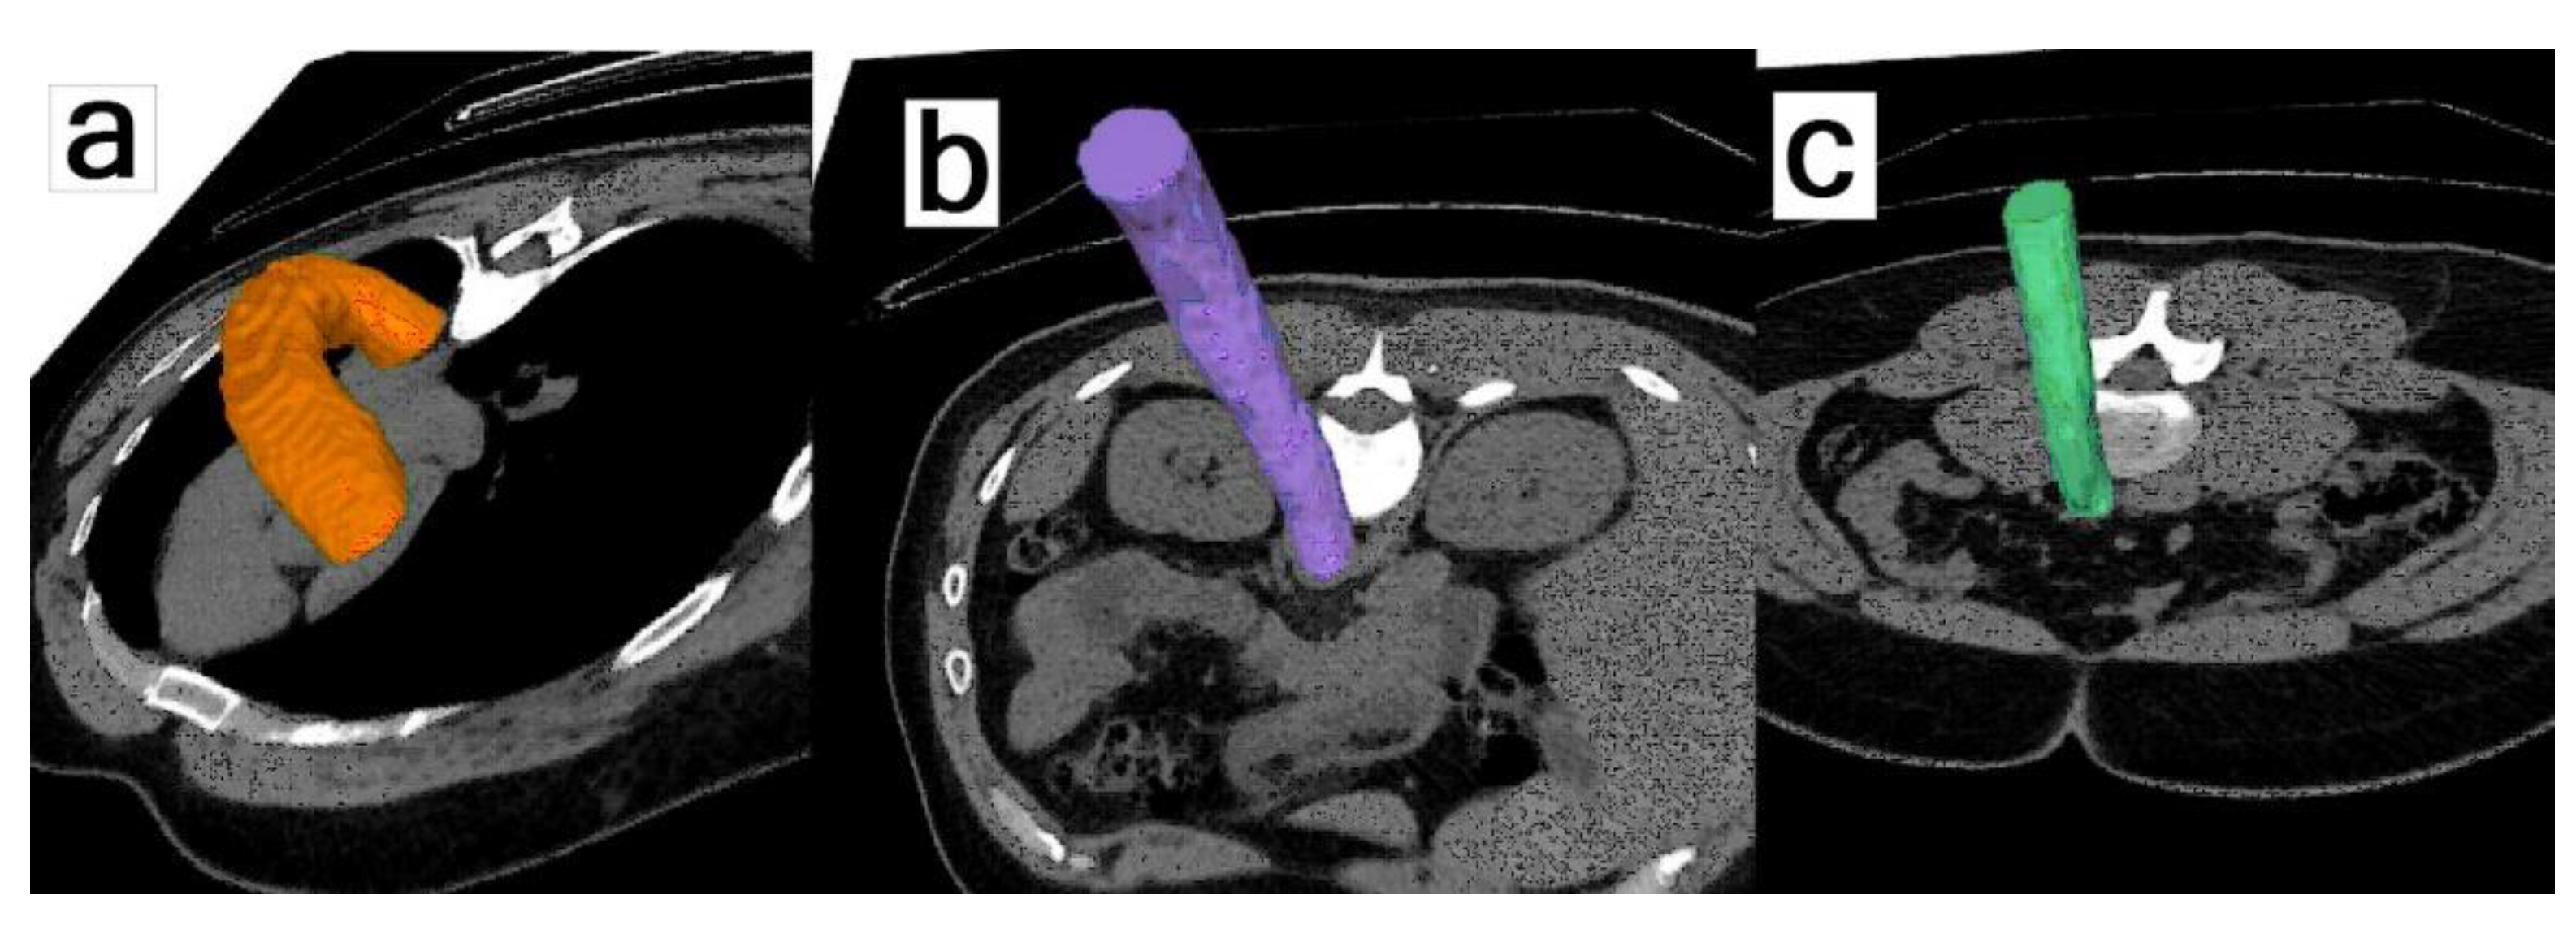

- Piri, R.; Edenbrandt, L.; Larsson, M.; Enqvist, O.; Nøddeskou-Fink, A.H.; Gerke, O.; Høilund-Carlsen, P.F. Aortic wall segmentation in 18F-sodium fluoride PET/CT scans: Head-to-head comparison of artificial intelligence-based versus manual segmentation. J. Nucl. Cardiol. 2022, 29, 2001–2010. [Google Scholar] [CrossRef] [PubMed]

- Piri, R.; Edenbrandt, L.; Larsson, M.; Enqvist, O.; Skovrup, S.; Iversen, K.K.; Saboury, B.; Alavi, A.; Gerke, O.; Høilund-Carlsen, P.F. “Global” cardiac atherosclerotic burden assessed by artificial intelligence-based versus manual segmentation in 18F-sodium fluoride PET/CT scans: Head-to-head comparison. J. Nucl. Cardiol. 2022, 29, 2531–2539. [Google Scholar] [CrossRef] [PubMed]